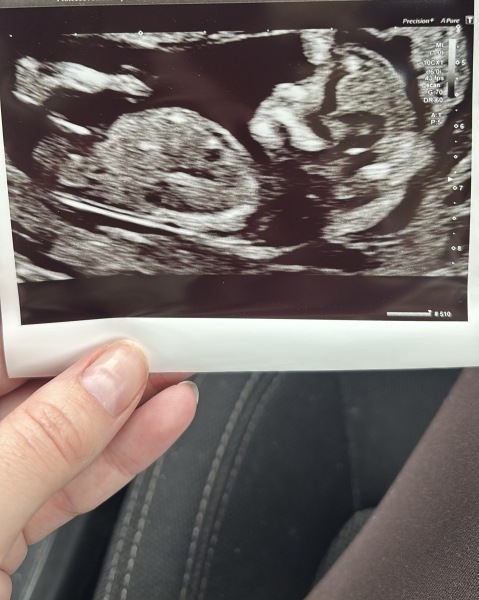

noaddedsugarx · 19/10/2023 18:26

@Goalhappy btw just to give you a bit of hope I’ve been researching and I’ve found 40+ images online where the nub looked really boyish and it turned out girl. it probs won’t happen for me but it does happen!

Here’s some